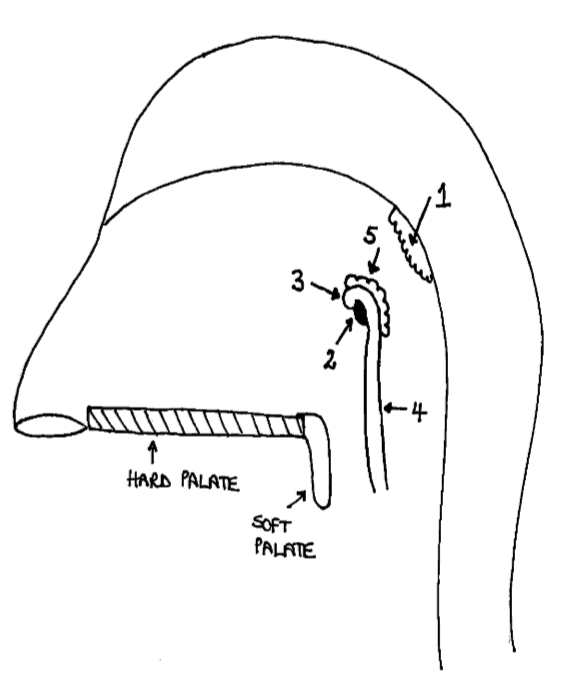

What is the anterior wall of 1?

posterior nasal choanae

What is the roof of 1?

body of sphenoid and basilar part of occipital

What is the posterior wall of 1?

anterior arch of atlas covered in pharyngobasilar fascia

What is the floor of 1?

soft palate

What is 1?

pharyngeal tonsil

What is 2?

pharyngeal opening of pharyngotympanic tube

What is 3?

tubal elevation

What is 4?

salpingopharyngeal fold

What is 5?

tubal tonsil